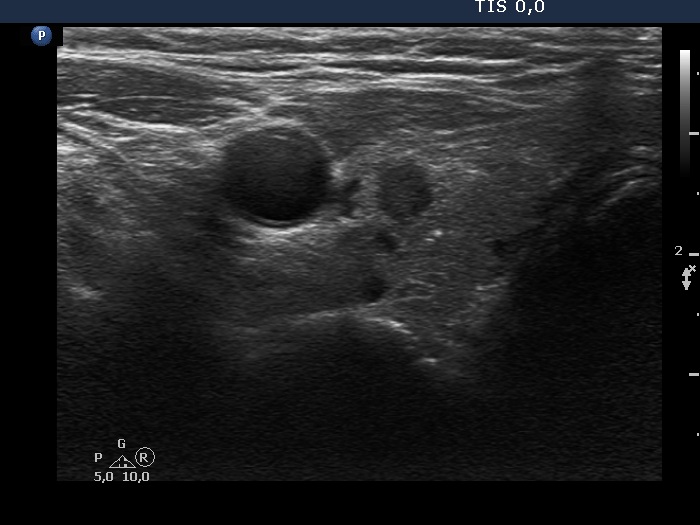

Ultrasonography. The thyroid was minimally hypoechoic and has several discrete lesions. A hypoechoic one in the left lobe showed both taller-than-wide and taller-than-long shape. There was a dominantly solid nodule in the lower part of the right lobe. There was a hypoechoic nodule in the upper, ventromedial part of the left lobe. This was the only lesion which was larger than 1 cm. This had a bit elongated hyperechoic figure.